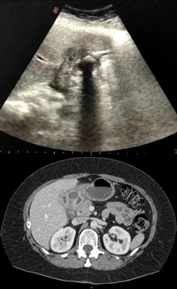

Una paciente femenina de 52 años, con antecedentes de obesidad y diabetes, ingresó a la guardia por dolor de tipo cólico en hipocondrio derecho asociado a vómitos de dos semanas de evolución. Se realizó una ecografía abdominal observando la vesícula biliar colapsada y una imagen hiperecogénica de 2x2 cm con sombra acústica posterior compatible con macro cálculo en bacinete, próximo a la pared duodenal (Fig.1. superior). La vía biliar, intrahepática y extrahepática, no se encontraba dilatada. La tomografía computada con contraste endovenoso mostró hallazgos similares. (Fig.1. inferior).

Fig.1. Imágenes preoperatorias

Superior: Ecografía, imagen hiperecogénica compatible con macro-cálculo en bacinete vesicular en contacto con duodeno.

Inferior: Tomografía axial computada se observa imagen hipodensa en íntimo contacto con pared duodenal.